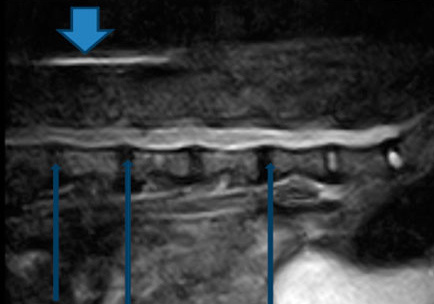

Рис. 1. МРТ таксы, которую лечили пиявками. Толстая стрелка - действие пиявок на подкожную клетчатку. Отек. Тонкими стрелками показана компрессия спинного мозга. Остается загадкой, как пиявки могут воздействовать на гиалиновый хрящ, вызвавший компрессию. Ответ прост: никак! 70 % такс выздоравливают самостоятельно, именно на этом фате основано псевдолечение пиявками, хондролоном и другими пищевыми добавками.

Таким же бесполезным для больных этой группы является лечение с использованием пиявок, кроме отека подкожной клетчатки в месте укуса пиявки, эти процедуры не дают никого эффекта.